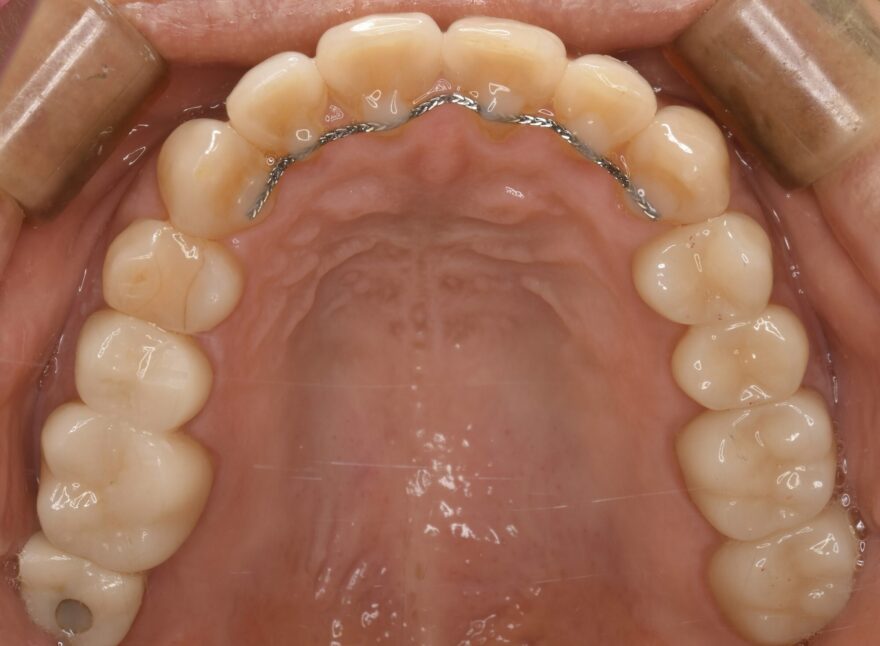

治療後の口腔内写真

なお前歯には、後戻り防止のためのワイヤーを装着しています。